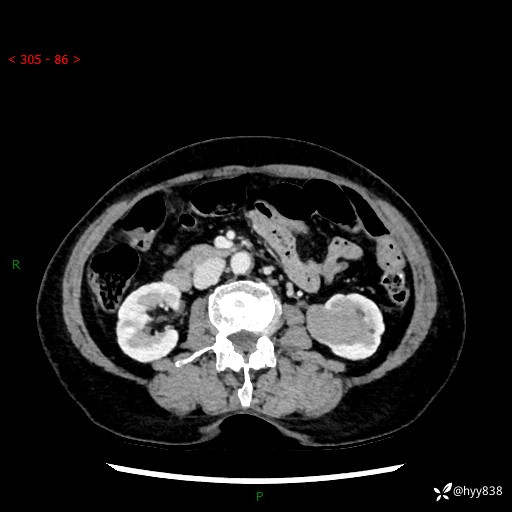

72岁/女,检查发现左肾占位1天。为了满足诊断,常规四期后,又加了延迟期-结果公布~

【患者信息】:72岁/女

【主诉】:检查发现左肾占位1天

【现病史及既往史】:患者于1天前检查发现左肾占位,无畏寒发热,无咳嗽咳痰,无腰腹部疼痛不适,无肉眼血尿、无尿频尿急症状,起病来,患者未行特殊治疗,为求进一步诊治,门诊以"左肾占位"收治入院。 发病来患者精神、饮食、睡眠良好,小便如上,大便正常,体重无明显变化。

【检查】:肾脏CT平扫+增强